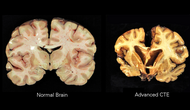

>es mejor para el cuerpo practicar un deporte que hacer ejercicios repetitivos Generalización muy descabellada porque depende exclusivamente del deporte al que te refieres. Por ejemplo los deportes de contacto como el boxeo tienen enormes tasas de encefalopatía traumática crónica, lo mismo con el futbol americano. Hasta el maratón tiene sus riesgos asociados.

>>11795 Qué riesgos tiene correr?, alguno cognitivo? Pregunto no irónicamente, me preocupa mi salud cognitiva porque me expuse mucho a drogas y falta de "ejercitación mental" desde que salí del colegio. Aparte, por temas psicólogicos y conductuales, necesito y estoy haciendo boxeo pero me preocupa que si avanzo al sparring, dañe aun más y de forma definitiva mi cerebro e incluso me da miedo llegar a convulsionar o que me dé un ACV (ya convulsioné como 4 o 5 veces tomando tramadol y en el SPEC cerebral que me hice, aparecen daños cognitivos, incluso bajé mi IQ, aunque no por tanto).